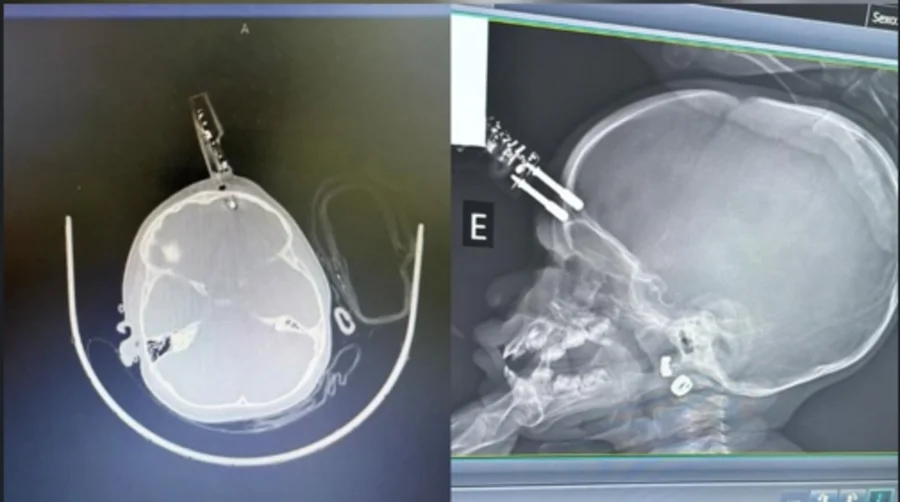

Uma menina de 1 ano passou por cirurgia de urgência, na terça-feira (13/1), após cair da cama e ter um carregador cravado na testa em Divinópolis (MG). De acordo com os médicos, a criança segue em observação e, até o momento, não apresenta sinais de sequelas neurológicas.

O neurocirurgião Bruno Castro, responsável pelo atendimento, informou que a mãe do bebê havia ido ao banheiro no momento do acidente. A criança estava com o carregador na mão quando caiu da cama, e acabou com o objeto cravado na cabeça.

A criança foi levada para a sala de cirurgias onde passou por procedimentos de limpeza, retirada do objeto, lavagem, fechamento e reconstrução da área atingida.